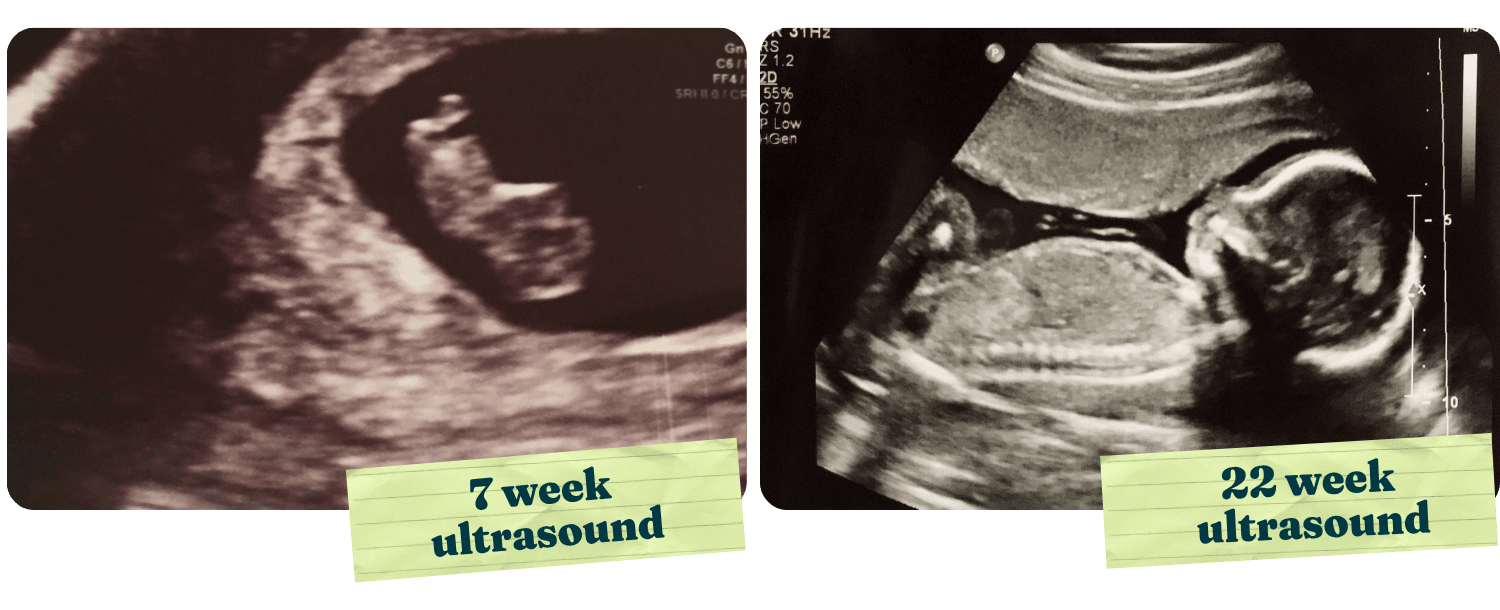

We brought her back for an ultrasound. In early pregnancy, it often takes some maneuvering to find the right angle, to locate the yolk sac and catch that tiny "gummy bear" image of a life beginning to grow. This time it was different. The moment the ultrasound probe touched her abdomen, it was immediately clear; this was not an early pregnancy.

There was no searching, no adjustment. She wasn't freshly pregnant. She was much further along. The patient stared at the screen in shock. "That's a whole baby!" she exclaimed.

I sat beside her and held her hand. It was the first ultrasound I had ever witnessed, and together we sat in awe, taking in the image of a fully-formed baby in her womb. The nurse continued the scan, measuring and capturing images. As the patient saw the baby's organs, bones, hands, and feet, her anxiety began to melt away. The fear that something was wrong was replaced with visible relief and wonder.

"I need to call my mom," she said. "I'm 22 weeks pregnant! I need to go shopping."